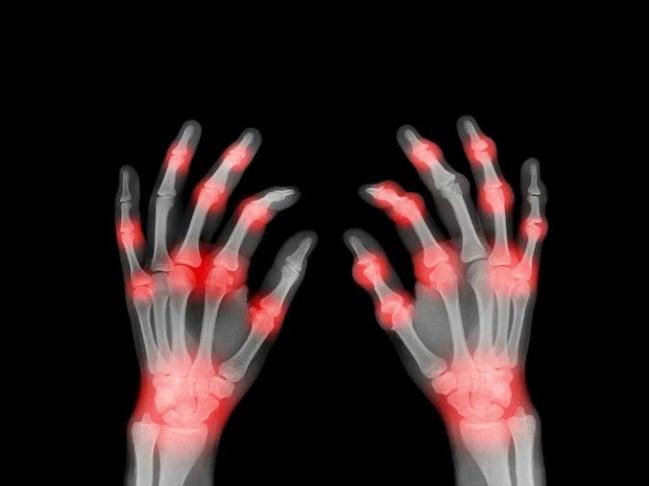

痛风常在夜间或清晨突然发作,疼痛感像刀割,最常受影响的部位是大拇趾,脚踝、膝盖、手腕、手指等关节也可能受到影响。发作时,患处会迅速红肿,摸上去发烫。急性发作的剧痛会在数天到两周内自行缓解,但这不代表痊愈,多数患者会在一到两年内复发。如果长期不控制,血液中过高的尿酸会形成“痛风石”,可能导致关节畸形、活动受限。